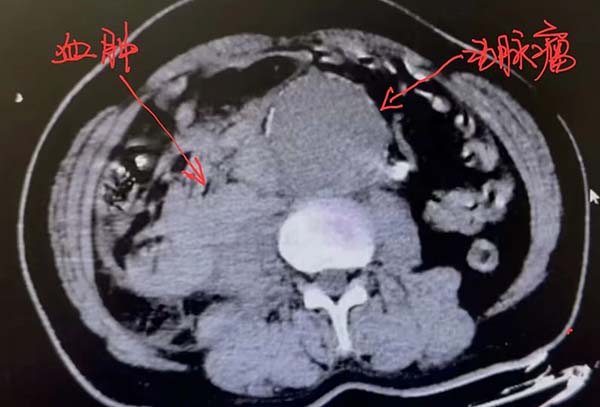

急诊团队第一时间启动抢救程序,患者休克低血压心跳增快,即刻补液、抗休克治疗,并迅速完成腹部CT平扫。普外中心血管外科住院总医师王杨博士紧急会诊,确诊为“腹主动脉瘤破裂,失血性休克”。患者腹主动脉瘤直径高达85mm,并破裂腹腔出血,肚子里有大量积血,腹主动脉瘤破裂是血管外科最危重的急症之一,随时可能死亡。

患者术前CT